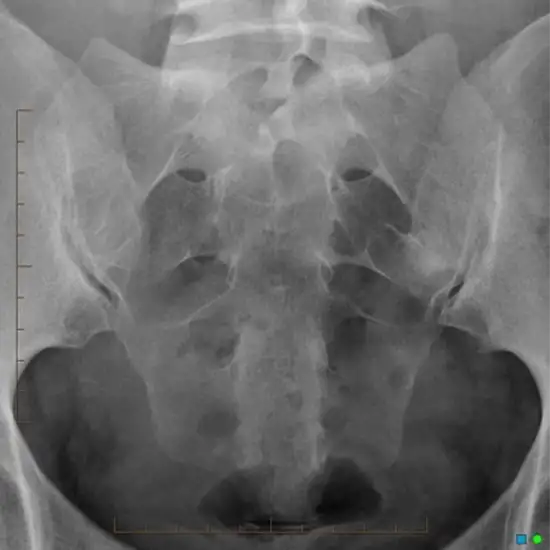

The sacroiliac joint is a joint that connects the hip bones to the sacrum. X-ray of both sacroiliac joints ap and lateral view is a radiographic procedure that records the image on a special x-ray film to view the area of the back where the spine connects to the hip bones.  The black and white image shows the bones, which appear white and softer body tissues.

Why is the X-Ray of Both Sacroiliac joints (SI Joints) AP And Lateral View Done?

Doctors order for X-Ray of Both Sacroiliac Joint (SI Joints) AP And Lateral View to diagnose

• Sacroiliitis

• Inflammation of the sacroiliac joint

• Spinal Arthritis (Ankylosing Spondylitis)

• If a patient experiences signs/ symptoms such as lower back pain, infection, inflammation, etc.

• If the doctor suspects the presence of deformities, abnormal mass growth, or tumor.

• To detect bone fracture in the SI joint region.